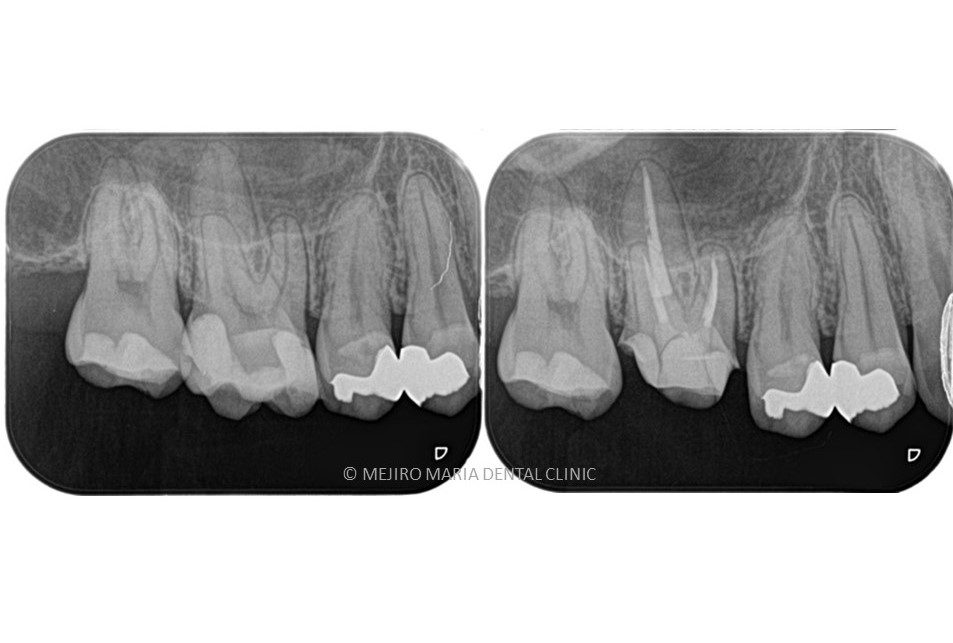

|歯の寿命を左右する初回根管治療_術前術後のレントゲン画像比較-1024x756.jpg)

根管治療において初めての根管治療(抜髄処置)が、その後の歯の寿命を左右する非常に大切な治療になります。 しっかりとコンセプトに沿った根管治療を行うことでより将来的な根尖性歯周炎(骨の中にまで炎症が進行しご自身の歯を残せなくなる場合もあります)になるリスクを最小限に抑えることができます。

コンセプトに沿った治療を行うことで成功率は96%と言われていますが、その成功率は術者の熟練度、治療環境により大きく変化するともレビュー論文で多く報告されています。

「再治療のリスクを下げる」➡「再治療による歯質削合を防ぐ」➡結果、歯の物理的な強度の保存につながります。 初めの根管治療を適切に行うことで、再度治療が必要になるリスク下げることができます。それは再治療の際にご自身の歯をまた削り、歯が弱くなってしまうことを防ぐことになるのです。

「歯の強度の低下」は「歯根破折(歯の根が割れたりひびが入ったりすること。抜歯になる可能性が高い)」のリスクを上げてしまうためこうした抜髄処置(初回根管治療)の時に歯科用顕微鏡を用いて、最大限の歯質保存をすることで治療の費用対効果が高くなる可能性があると考えられます。